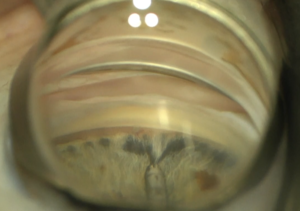

Goniosynechialysis

This video covers basic techniques for successful completion of goniosynechialysis (GSL) with Tips and Tricks for success. Surgical videos are utilized to illustrate various techniques by different surgeons.